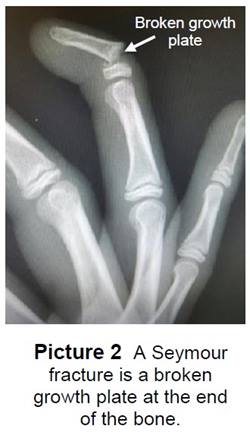

Fracture of a Bone

- It is very important to get bone fractures treated right away to prevent future problems.

- Crush injuries to the fingertip can cause 2 types of bone fractures:

- Seymour Fracture - a break in the growth plate (Picture 2).

- Tuft fracture - a break in the bone closest to the tip of the finger.

- Both types of fingertip fractures are treated with a splint or cast.

- These keep the bone from moving so it will heal.

- Your child may wear the splint or cast for 2 to 4 weeks.